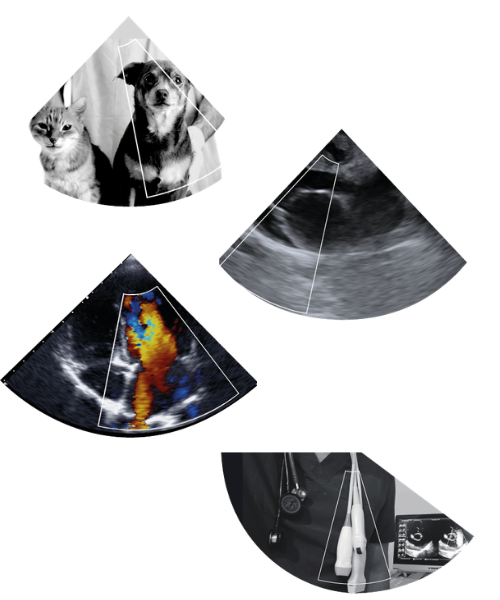

Soy Médico Veterinario y Especialista en Cardiología Veterinaria, dedicado a la medicina cardiorrespiratoria en pequeños animales. Dirijo Cardioimagen, una clínica enfocada en medicina cardíaca y cardiorrespiratoria, así como en el cuidado integral del paciente geriátrico. Mi trabajo se orienta a promover una medicina preventiva que permita no solo tratar enfermedades, sino también mejorar la expectativa y calidad de vida en perros y gatos.

Mi práctica clínica integra cardiología, ecocardiografía, ultrasonido cardiotorácico, medicina geriátrica y nutrición clínica preventiva, abordando al paciente considerando su etapa de vida, sus comorbilidades y su entorno familiar.

Soy autor del libro “Ultrasonido Clínico Torácico en la Práctica Veterinaria. Un Manual en Movimiento”, enfocado en convertir la ecografía en una herramienta clínica práctica y accesible.

La ecografía torácica veterinaria se ha convertido en una herramienta fundamental para el diagnóstico de enfermedades pulmonares, pleurales, mediastínicas y de la pared torácica en pequeños animales.

Este manual práctico y visual entrega al médico veterinario una guía clara para interpretar hallazgos ecográficos y apoyar la toma de decisiones clínicas de manera segura y eficiente.

Guía práctica de ecografía torácica en pequeños animales para la toma de decisiones clínicas